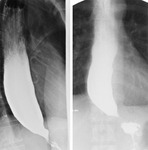

Acalasia

Aparência clássica do esôfago dilatado com estreitamento em bico afunilado no estudo baritado

Do acervo do Dr Jin-Yong Kang; usado com permissão